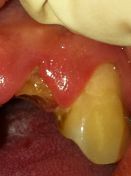

L’utilizzo del Laser a diodi nei casi di denti fratturati o rovinati dalla carie si rivela di notevole aiuto, data la possibilità di lavorare in campo asciutto (senza sangue). Se si aggiunge, a questo, la possibilità di rimodellare il bordo gengivale fa del Laser a diodi uno strumento di elezione in queste tematiche. Il caso in esame tratta di un incisivo laterale sup. destro fratturato da circa un mese per una carie che interessava parte del colletto dentale, si noti come la gengiva abbia modificato il suo assetto coprendo buona parte del moncone. Il Laser a diodi in questo caso ci ha permesso di rimodellare il bordo gengivale, di allungare la corona clinica e ci ha dato la possibilità di inserire un perno endo-canalare senza grosse difficoltà permettendoci di lavorare in asciutto.